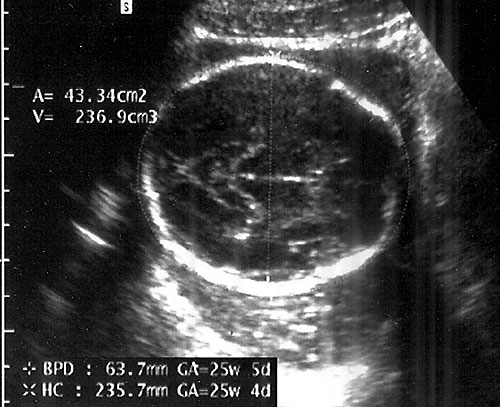

Measurements from outer edge at superior margin to inner margin at inferior margin to correct for fetal skull thickness (left). Proper measurement of head circumference (right). - Clinically meaningless, unless multiple parameters are measured and evaluated.

- Measuring BPD/HC

- Axial plane at level of septum cavum pellucidum and thalamic nuclei. (Shepard M, Filly RA. A standardized plane for bieparietal diameter measurement. J Ultrasound Med 1982;1(4):145-50.)